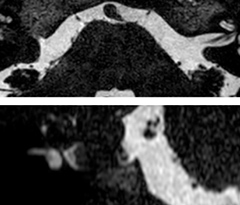

A two year follow-up scan of a CPA meningioma using both Ingenia 3.0T without CS and Ingenia Elition 3.0T with Compressed SENSE allows for a nice comparison to demonstrate the protocol improvements achieved on the Elition: 3D FLAIR has a shortened scan time, improved SNR and still the same spatial resolution. BrainView (3D T1 TSE) has improved spatial resolution and SNR with shortened scan time. For 3D T2 Drive the spatial resolution has been improved. 3D THRIVE used to have an interpolated 0.8 mm slice thickness, but true thickness at 1.6 mm, so that axial slices displayed a decent quality, but reformats were suboptimal. Compressed SENSE is used on Elition to improve spatial resolution and reduce the non-interpolated slice thickness to allow smoothly reformatted images. Total scan time (adding SmartBrain and an additional b2000 diffusion) was 13:19 on Ingenia, and is now reduced to 10:42 on Ingenia Elition.

Ingenia 3.0T (without Compressed SENSE)

3D FLAIR 1.0 x 1.0 x 1.0 mm* 4:24 min.

3D TSE T1w 1.0 x 1.0 x 1.2 mm* 2:40 min.

3D T2w Drive 0.8 x 0.8 x 1.0 mm* 3:05 min.

3D T1w THRIVE 0.8 x 0.8 x 1.6 mm* 1:30 min.

Ingenia Elition 3.0T with Compressed SENSE

3D FLAIR 1.0 x 1.0 x 1.0 mm* 2:50 min.

3D TSE T1w 1.0 x 1.0 x 1.0 mm* 2:10 min.

3D T2w Drive 0.7 x 0.7 x 0.7 mm* 2:52 min.

3D T1w THRIVE 0.7 x 0.7 x 0.8 mm* 1:30 min.

*true voxel size, without interpolation